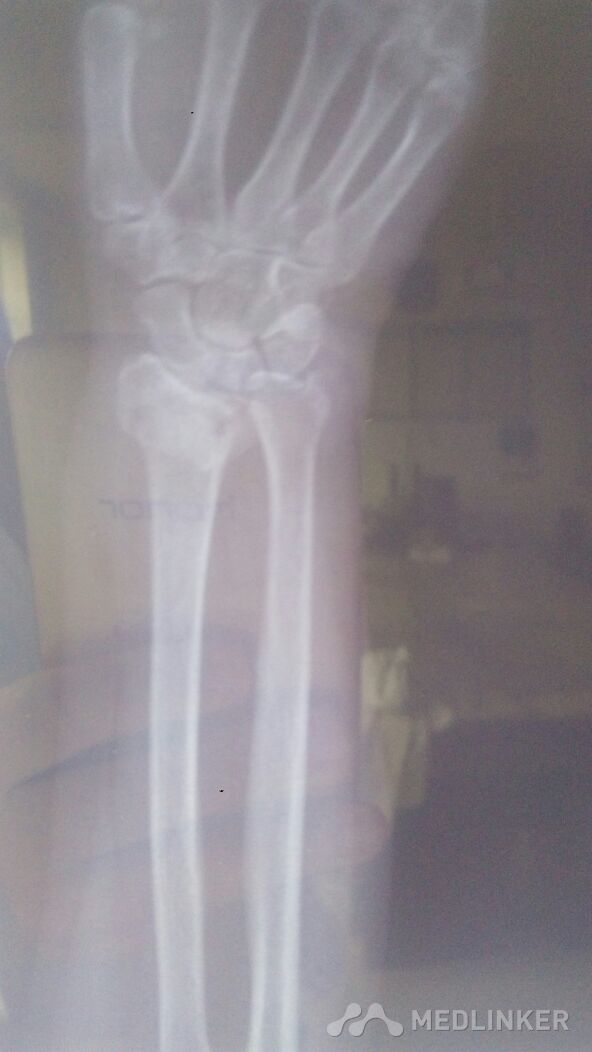

左桡骨远端骨折,左尺骨茎突骨折。

左腕部外伤后,血压高压210.低压110.左腕疼痛,畸形明显。手法复位。

左腕部外伤后,畸形明显伴疼痛。左手末梢感觉麻木。左腕部活动受限。

左桡骨远端骨折,左尺骨茎突骨折,手术治疗。

已经尽力了。尺偏,北侧仍然移位。血压太高。不手术治疗,不行啊!家属不愿手术治疗。怎么办?